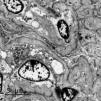

Internal medicina requested evaluation by nephrology due to deterioration of kidney function with a result of proteinuria of 8g in 24h. This way, taking of a renal biopsy is ordered, and is subjected to light microscopy, immunofluorescence and electron microscopy, with a report of podocyte lesion of 70% associated with glomerulosclerosis. focal and segmental (FSGS), severe acute tubular necrosis, interstitial fibrosis with moderate tubular atrophy and pigment casts. Thus, histochemistry was performed with a positive reaction for iron with evidence of intraluminal and cytoplasmic granular deposits in the proximal tubules compatible with hemosiderin and is negative for hemoglobin. During follow-up, she developed severe hyperkalemia refractory to medical management, requiring a single session of renal replacement therapy with hemodialysis. It was determined that the deterioration of renal function was evidenced by pigment cast nephropathy related to sickle cell disease.

In this particular case, the presence of pigment casts with a negative result for hemoglobin in immunohistochemistry was identified, which is why histochemistry was performed with positive staining for hemosiderin, indicating the presence of a pigment derived from hemoglobin. Pigment cast nephropathy was diagnosed, a condition in which renal function deteriorates due to the toxic effect of pigments containing the heme group. This condition can be caused by various causes, such as rhabdomyolysis (myoglobin pigment), cholestasis (bile acid pigment), and, as in this case, intravascular hemolysis (hemoglobin pigment). It is important to highlight that the presence of hemoglobin casts is rare, and what is described here is the accumulation of hemosiderin in the proximal tubule, as occurs in sickle cell crisis, where there are frequent and persistent episodes of hemoglobinuria.7,8 Furthermore, findings compatible with acute tubular necrosis (ATN) were observed in this patient. It is relevant to note that when ATN occurs alone, without cast nephropathy, special stains in immunohistochemistry do not detect hemoglobin and myoglobin, as happened in this case. It is important to keep in mind that, in case series of patients with pigment cast nephropathy, 100% of cases present acute tubular injury.9–11

Hematoxylin–eosin stain – 4×. In the sample, 10 glomeruli were identified, 4 of them with global sclerosis (40%) and 1 with segmental sclerosis of a non-specific pattern. The evaluable glomeruli present open capillary loops, preserved mesangial matrix, marked podocyte activation, one with hyalinosis and segmental sclerosis, another with periglomerular fibrosis; without significant alterations in the glomerular basement membrane with the special stains. Casts of brown granular and intracytoplasmic epithelial material predominant in proximal tubules. Signs of acute tubular damage with loss of the brush border, luminal dilation, thinning of the lining epithelium, peeling of cells towards the lumen, in 50% of the sample. Interstitial fibrosis and tubular atrophy, moderate arteries, arterioles and peritubular capillaries, without obvious alterations.